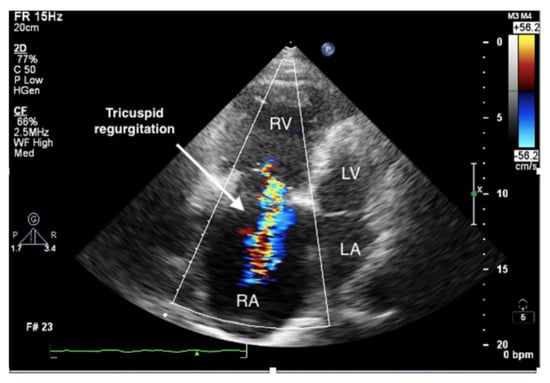

Figure 4.

Enlarged right ventricle and right atrium. Tricuspid regurgitation. 2D-TTE, RV-focused apical 4CH view.